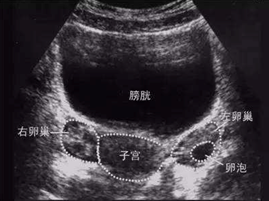

徐医生调出以下2张图片告诉翟女士:

图示1为B超监测下的卵巢和发育的卵泡,当卵泡发育至一定的经线,结合血激素的结果可以确定合适的取卵时间。

图示1